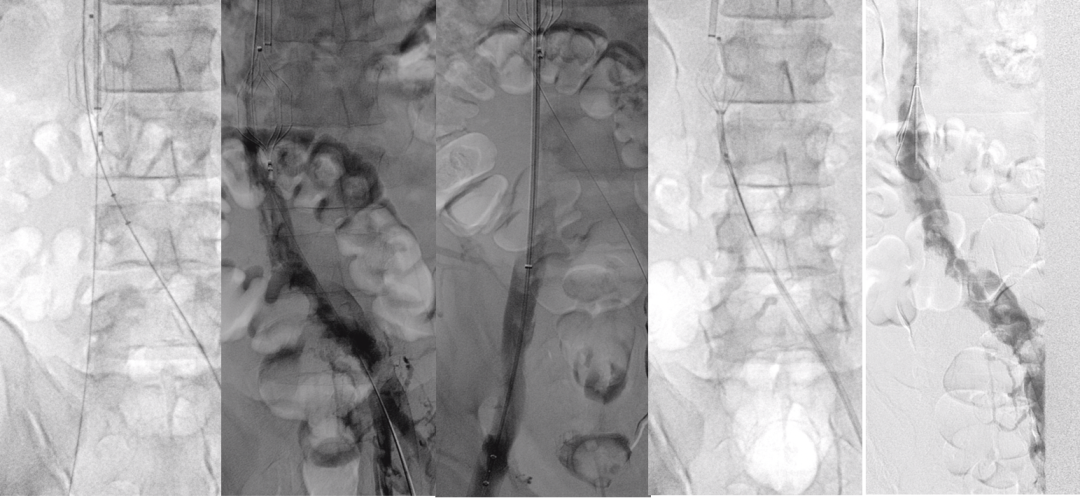

★ Case5:儿童(13岁)IVCT致下腔静脉闭塞

图:第一次手术

图:第二次手术

图:第三次手术